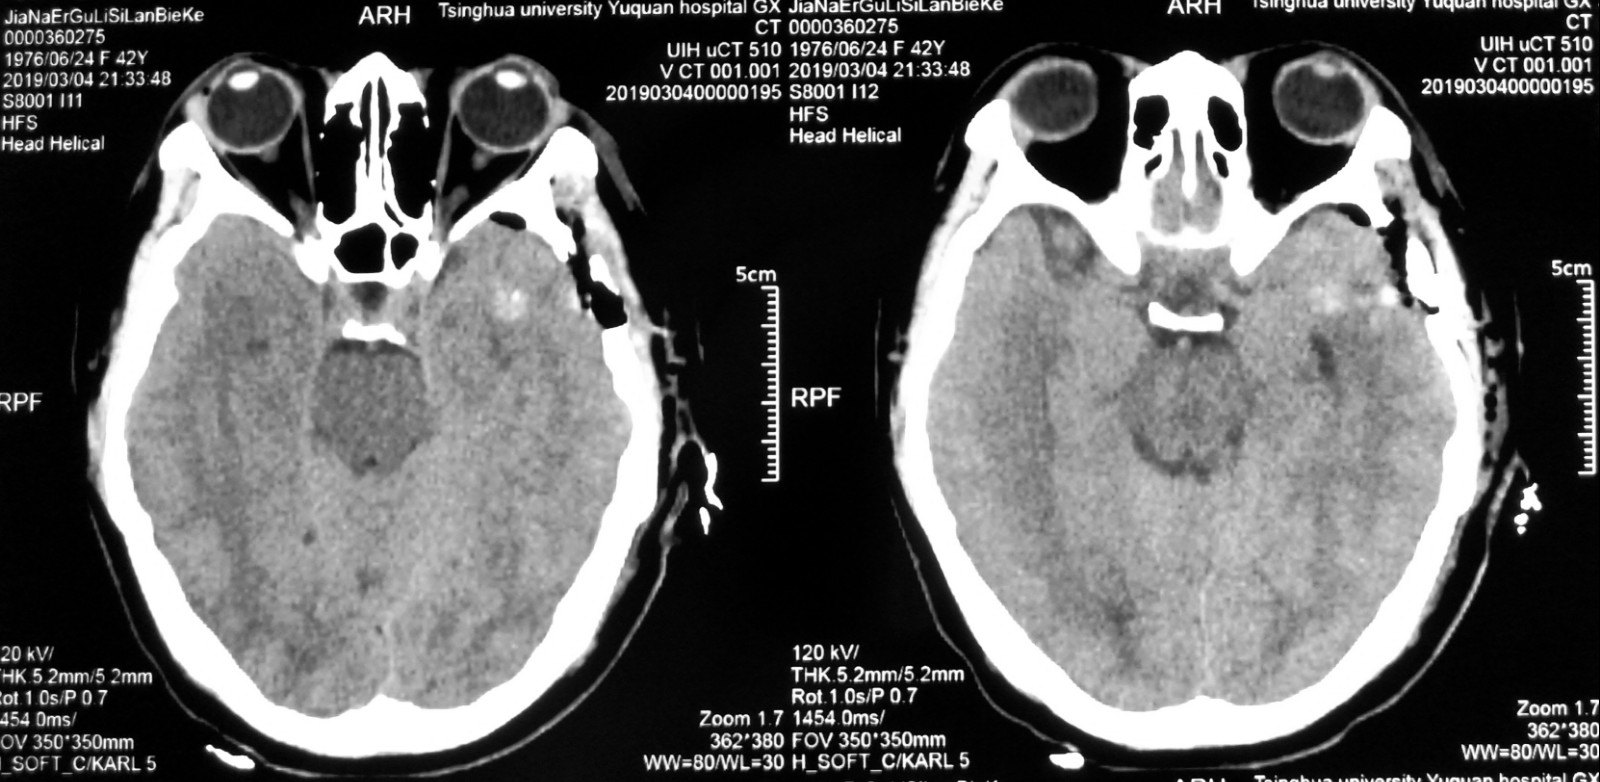

ct及mri:颅内多发海绵状血管瘤,右侧颞叶病变出血. 神经导航下右侧颞

右侧颞叶海绵状血管瘤.

病例伴出血及脑软化的海绵状血管瘤一例ct及mr